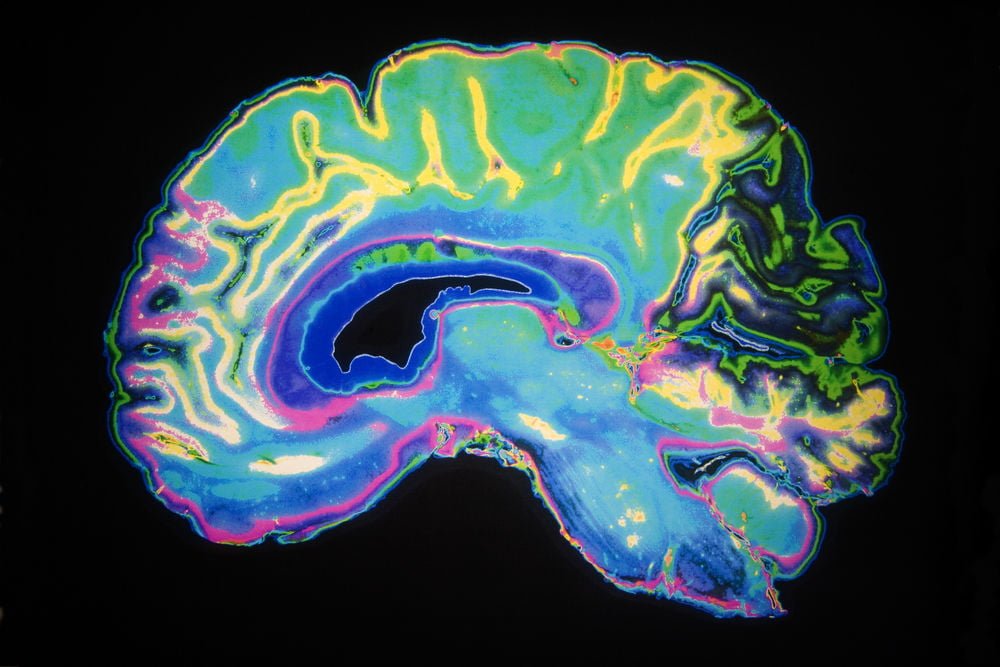

هرچند که تعداد بیماران در این تحقیق کم است اما نتایج قابل توجهی وجود دارد که این بیماران حداقل یک کپی از شکل خاصی از ژن APOE4 دارند که آنها را در خطر ژنتیکی بسیار بالایی در توسعه بیماری آلزایمر قرار میدهد. در حال حاضر بسیاری از پزشکان به دلیل عدم وجود درمان برای آلزایمر، بیماران را برای این ژن ارزیابی نمی کنند. با این حال بردسن ادعا می کند که ما در حال ورود به عصر جدیدی هستیم و ارزیابی ژن APOE4 در مراحل اولیه امکان جلوگیری از ابتلا به آلزایمر را برای بیماران فراهم میکند. تصویر زیرنمایی از MRI مغز یک بیمار مبتلا به آلزایمر را نشان میدهد که در نواحی خاصی از مغز کاهش حجم داشته است.

10نفری که در این مطالعه شرکت کرده بودند از بیماری آلزایمر یا اختلال شناختی خفیف و یا اختلال ذهنی رنج میبردند. با این حال پس از طی شدن دوره درمان در بسیاری از آنها دیگر علایم بیماری مشاهده نمیشد. به عنوان مثال مردی در اواسط دهه ی 60 زندگی خود که در بخشی از مغز خود به نام هیپوکامپ دچار کاهش حجم شده بود و حجم آن به 17% رسیده بود بعد از 10 ماه درمان حجم هیپوکامپ مغز آن به 75% افزایش یافته و علاوه بر این به بهبود عمده ای در ظرفیت های شناختی خود دست یافت. مرد دیگری در اواخر دهه ی 60 زندگی خود که حافظه ی بلند مدت او عملکرد مناسبی نداشت به دلیل اینکه عوارض بیماری در آستانه تعطیل کردن کسب و کار بود. وی پس از 6 ماه درمان قادر به حفظ برنامه کار خود و شناخت همکاران خود بود. بردسن در خصوص موفقیت این درمان در میان روش های درمانی بیشمار توضیح میدهد که: “تصور کنید که این بیماری یک سقف با 36 سوراخ در آن است. دارو ممکن است که فقط یک سوراخ آن را به خوبی پر کند ولی همچنان نیاز به پر کردن 35 سوراخ دیگر نیز می باشد. بنابراین پروسه اصلی چندان تغییری نمیکند.”